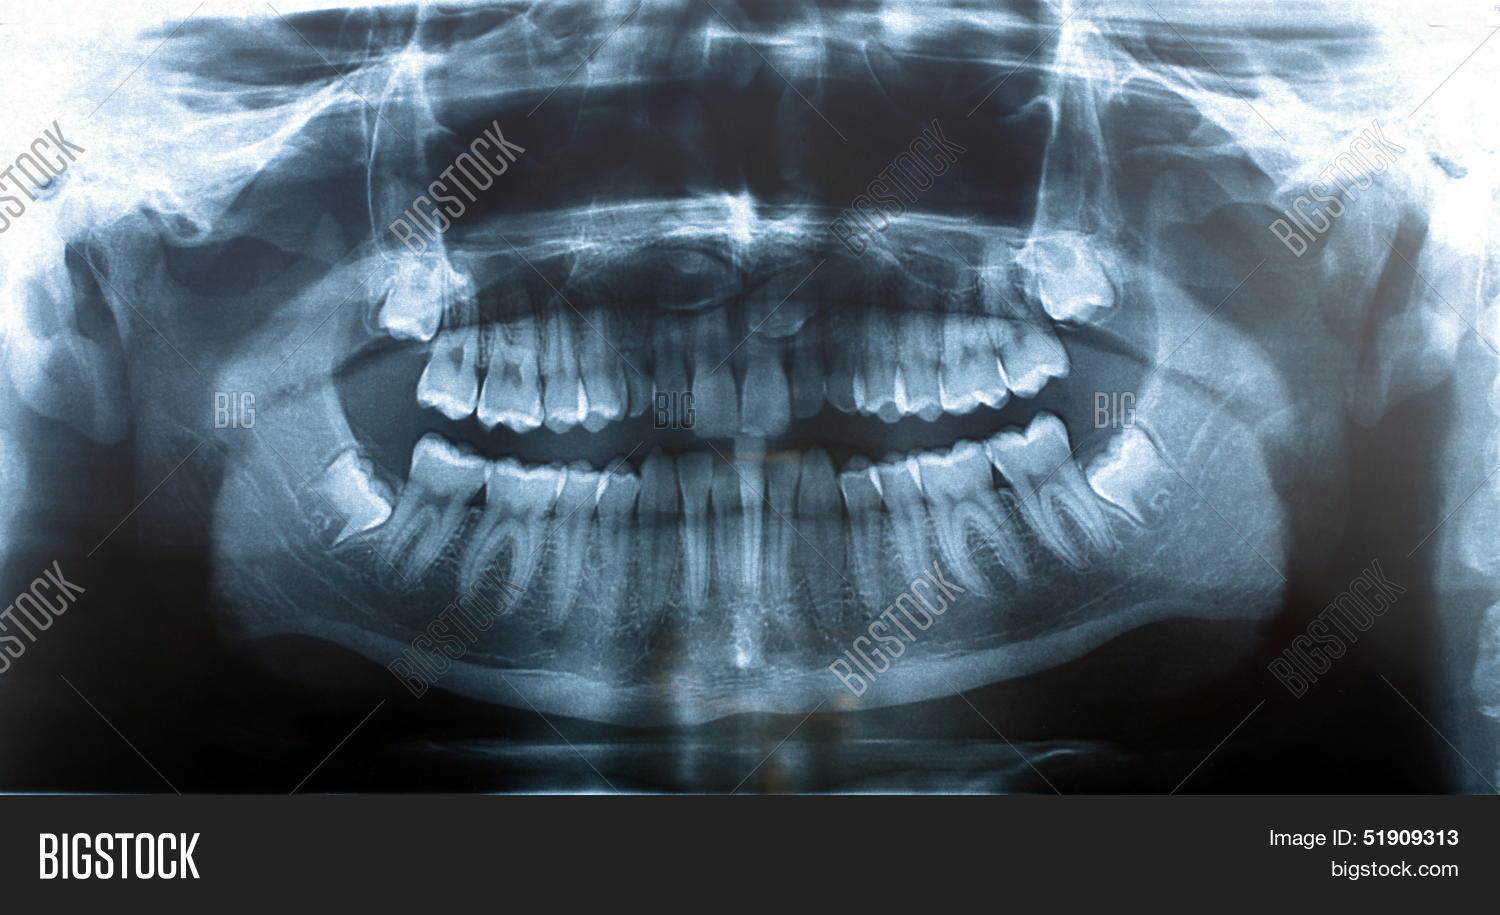

From www.dreamstime.com

Panoramic Xray of the Lower and Upper Jaw. Stock Photo Image of Jaw X Ray Views The temporomandibular joint (tmj) is an atypical synovial joint located between the condylar process of the mandible and the mandibular. Proper characterization of jaw abnormalities is essential to ensure appropriate patient care and reduce morbidity. Imaging plays a key role in the characterization of a variety of jaw lesions, and radiologists must be familiar with A properly positioned radiograph of. Jaw X Ray Views.